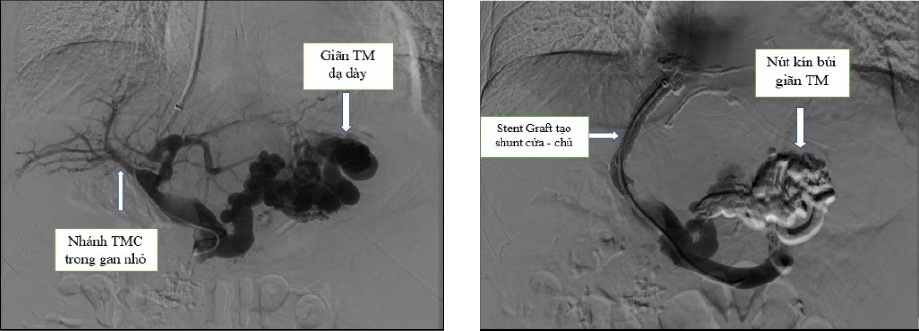

Ekip của Tiến sĩ Trần Quang Lục đã can thiệp cho người bệnh bằng kỹ thuật TIPS với sự hỗ trợ của hệ thống máy chụp mạch số hóa xóa nền DSA và các trang thiết bị hiện đại. Toàn bộ quy trình kỹ thuật được thực hiện trong lòng mạch máu với một vết chọc rất nhỏ tạo đường vào ở tĩnh mạch cổ. Sau khoảng 1 giờ can thiệp, các bác sĩ đã đặt một stent phủ vào trong gan, làm giảm áp lực tĩnh mạch cửa và nút tắc hoàn toàn các búi giãn tĩnh mạch thực quản. Sau 2 ngày theo dõi, người bệnh đã hoàn toàn ổn định, đi ngoài phân vàng, tình trạng chướng bụng giảm đáng kể, các xét nghiệm cải thiện tốt và được ra viện điều trị theo phác đồ tại nhà.

Tiến sĩ Trần Quang Lục cùng ekip thực hiện kỹ thuật TIPS với sự hỗ trợ của hệ thống máy chụp mạch số hóa xóa nền DSA và các trang thiết bị hiện đại.

Kỹ thuật TIPS trên một ca bệnh chảy máu do giãn tĩnh mạch dạ dày.